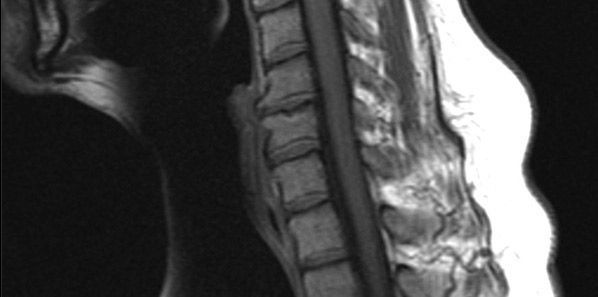

If the diagnosis of a cervical spine injury is missed in patients, it can result in devastating consequences. In some cases, CS injuries cannot be ruled out clinically using the National Emergency X-Radiography Utilisation Study low-risk criteria either because of a neurologic deficit or pain, and there may be a need to use other imaging tools. However, the optimal imaging modality for Cervical Spine (CS) clearance still remains controversial.

Over the years, Computed tomography (CT) of the cervical spine and Magnetic Resonance Imaging (MRI) has been used to evaluate trauma patients with neurologic deficits. MRI has often been employed as an imaging modality in order to exclude C-spine instability but research studies to date provide inconclusive data with respect to the necessity of using MRI for CS clearance.

A prospective observational study that was conducted from January 1, 2010 to May 31, 2011 at a level 1 trauma centre was to investigate the accuracy of CT and MRI for CS clearance. The study included 830 adults who were alert and awake and had experienced blunt trauma with resultant midline CS tenderness and/or neurologic deficits. Study patients were undergoing CT of the CS. Researchers recorded every patient's CS imaging results, interventions and final diagnosis. The criterion standard was based on the sensitivity and specificity calculations for the final diagnosis of CS injury at the time of discharge.

During the study, 164 CS injuries were diagnosed and 23 of these were found to be clinically significant. For the purpose of this study, clinically significant CS injuries were defined as injuries requiring surgical stabilization or halo placement. CT was able to detect all clinically significant injuries.

Out of the 681 patients, 15 patients with a normal CT scan had a newly identified finding on MRI. However, none of these injuries required any surgical intervention or halo placement. There was no specific need to change patient management on the basis of MRI findings. As far as sensitivity and specificity of CT for detecting CS injury is concerned, the results showed 99.9% and 100% accuracy. Both sensitivity and specificity was 100% for clinically significant CS injuries.

Based on the findings of this study, CT is effective in detecting clinically significant CS injuries in adults who were deemed eligible for evaluation due to neurologic deficit or CS pain. However, the study proved that MRI did not provide any additional clinically relevant information. It is unlikely that an MRI will uncover any unstable CS injuries in patients who have already been evaluated with CT.